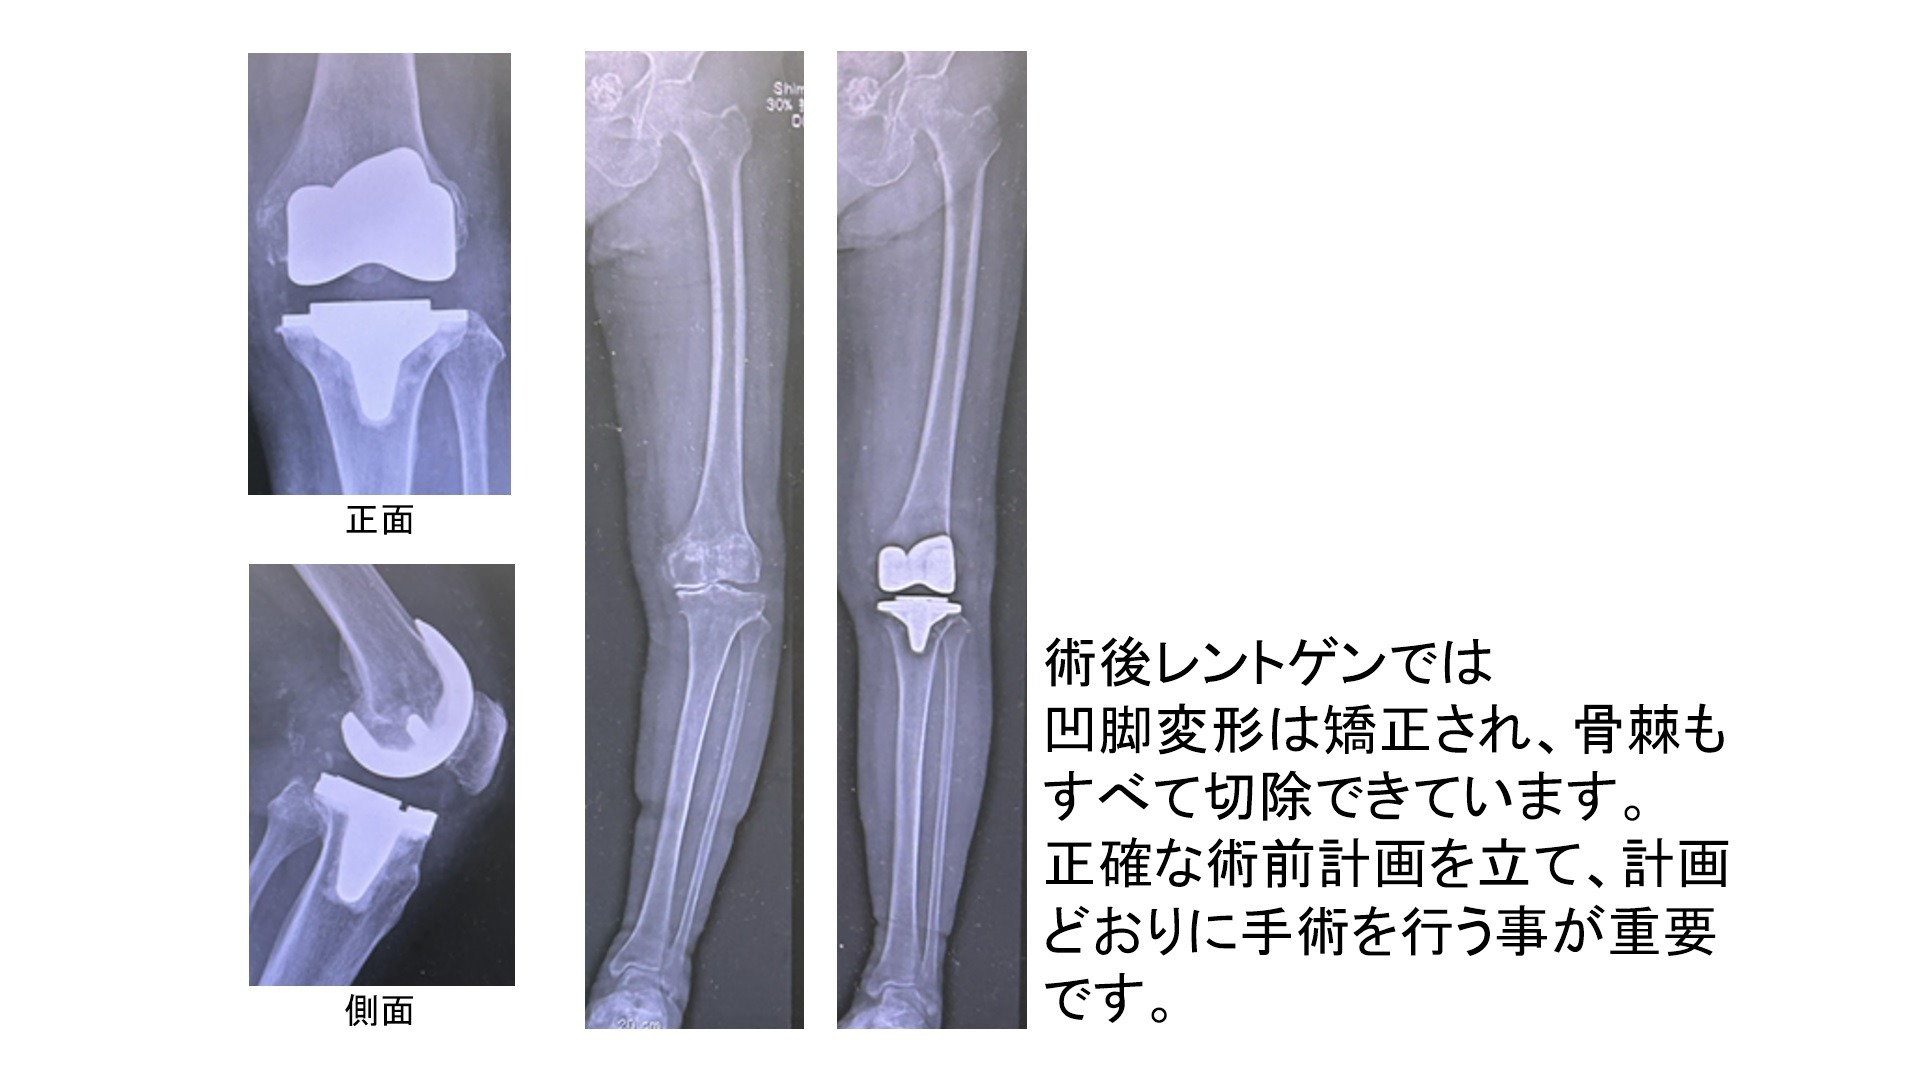

2.人工膝関節

変形した膝関節を再建するために1950年台にイギリスで開発され進化を遂げてきました。現在は大腿骨側で痛んだ骨を削ってコバルトクロム製の大腿骨インプラントを設置し、脛骨(すねの骨)側で痛んだ骨を削ってコバルトクロム製の脛骨インプラントを設置します。それらの間に軟骨の代わりになるインサート(高分子ポリエチレン)を設置して手術を終了します。変形の状態や疾患によっては膝蓋骨側もインプラント(高分子ポリエチレン)で置換する場合があります。

①CTを用いた三次元手術計画(LEXY社3次元術前計画支援ソフトを使用)を行います

患者さんごとに適切な人工関節の大きさ、形状、位置などを正確に決定することができます。